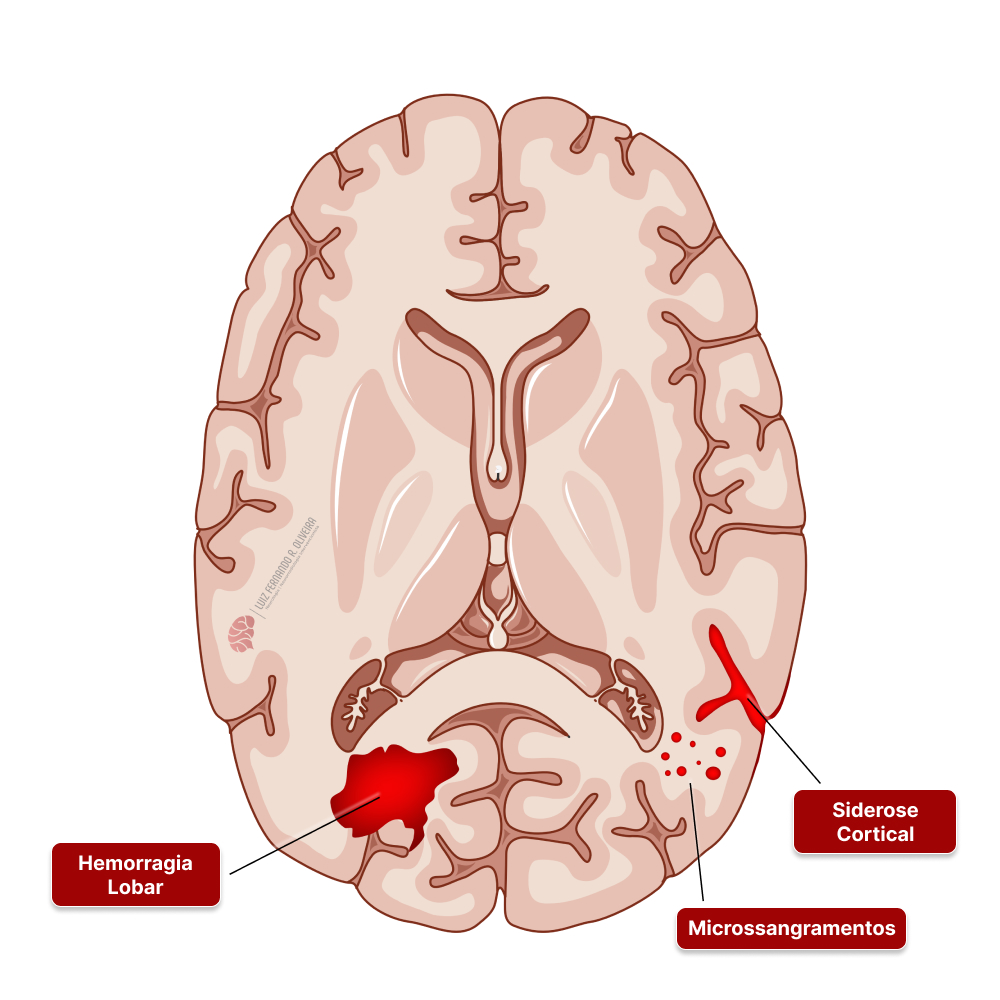

A angiopatia amiloide cerebral é outra forma de doença dos pequenos vasos cerebrais que pode levar a hemorragias.

Nesse caso, proteínas anormais chamadas de beta amiloide se depositam nas paredes das pequenas artérias próximas à superfície cerebral.

Esses vasos ficam enfraquecidos, com maior risco de vários tipos de sangramentos, desde microsangramentos (“microbleeds”), siderose cortical (sangramentos na superfície do cérebro) e hemorragias maiores ou lobares. Em alguns casos, os pacientes também podem ter demência.

Controlar a pressão adequadamente também ajuda a diminuir o risco de hemorragia cerebral por angiopatia amiloide cerebral